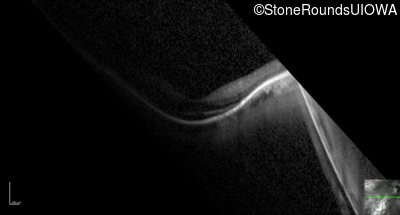

Optical Coherence Tomography - Right - 20/40 +2

Exemplar / OCT Stack